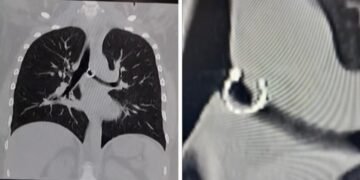

A través de este posteo, visto por más de cuatro millones de personas, aseguró haber aspirado un aro que llevaba en su nariz sin darse cuenta —lo hizo mientras dormía—, lo que le causó problemas de salud. Además, mostró radiografías e imágenes de la pieza de joyería.